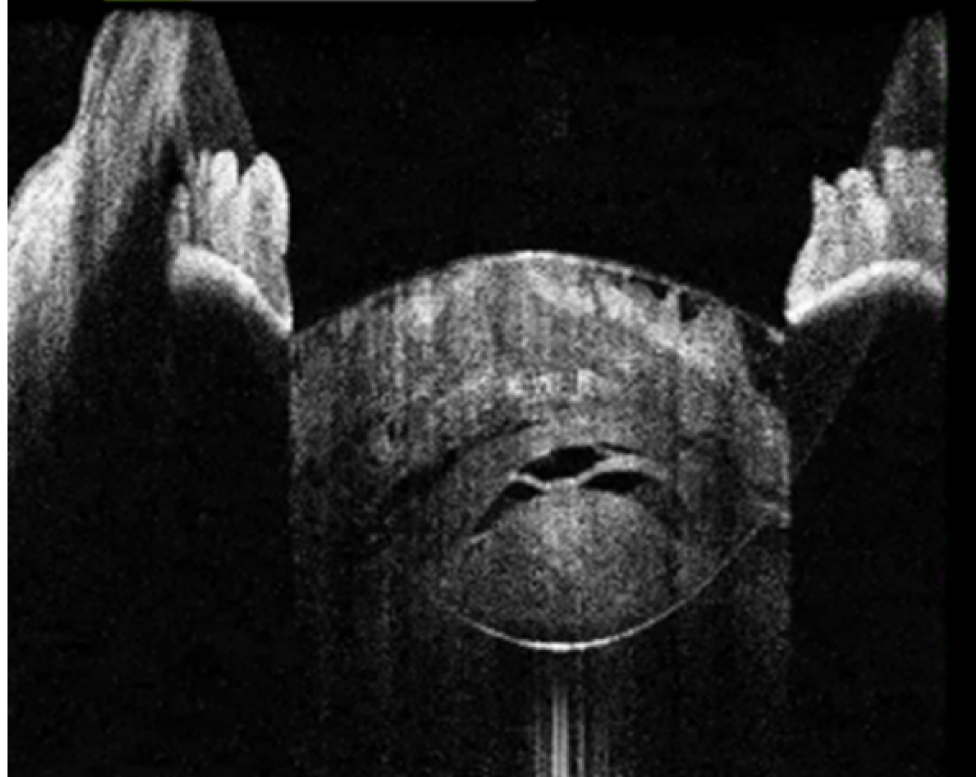

В исследование вошли 196 пациентов (250 глаз) с перезрелой катарактой. Пациенты были разделены на 2 группы (по 125 глаз в каждой группе). Всем пациентам интраоперационно с помощью интегрированной в операционный микроскоп И-ОКТ, Hi-R NEO (HAAG STREIT, Германия), определяли тип перезрелой катаракты (рис. 1–4).

Рис. 1. Тип 1 перезрелой катаракты: равномерно расположенные кортикальные волокна, минимальные внутрихрусталиковые щели, отсутствие оводнения кортикальных масс

Рис. 2. Тип 2 перезрелой катаракты: непрерывные гиперрефлективные полосы кортикальных волокон, множественные внутрихрусталиковые щели, оводнение хрусталика